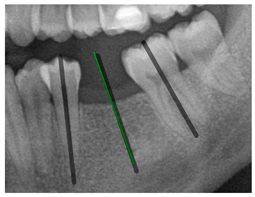

| Comparison with dentist’s ground truth (black line) and our framework (green line) | ||||||

| Validation Image 1–6 | ![]() | ![]() | ![]() | ![]() | ![]() | ![]() |

| MSE | 3.59 | 1.29 | 0.41 | 0.80 | ||